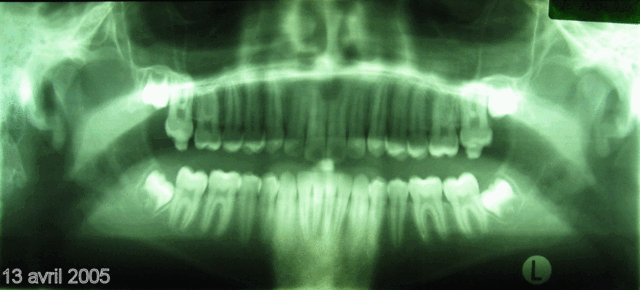

Bonjour, voici les clichés "panoramique" et "télé de profil" du 13 avril 2005 de Florent B. (voir les premiers posts pour comparer juillet 2001 et mars 2004 avec ce 13 avril 2005). J'espère que ces radios vous conviendront parfaitement pour les mesures? Aucun "trucage".

J'attends avec impatience et une grosse pointe de stress votre verdict clair, précis et concis sur l'évolution favorable ou défavorable du cas.

Ne faites pas durer le suspens trop longtemps : je n'en dors plus ! :-)

Je serai heureux si un ODF pouvait mesurer les valeurs 2001 et 2005 sur les téléRx et comparer celles-ci aux valeurs "normales" de vos tables de références.

Tout a été obtenu uniquement par REIOR (approx. x10, successifs) et GAL, cad en l'absence de toute force exogène.